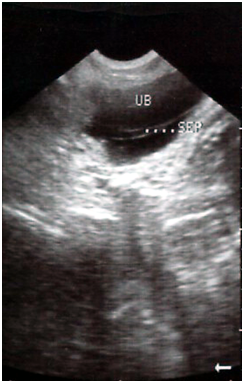

A 7year old boy reported with pain periumbilical area and passage of worms with the stool. No history of vomiting, fever or constipation was present. Past history did not reveal any significant. General physical examination as well as systemic examination was normal. Per abdominal examination revealed distension and a palpable worm mass in umbilical quadrant. Per rectal findings could not reveal any significant. Blood counts and a urine examination were normal. X-ray abdomen showed gut distension. Ultrasonography abdomen showed multiple worm masses in gut. There was an incidental finding of an echogenic band in the bladder extending upto middle of bladder vertically and a small thickening of posterior bladder wall seen on ultrasonography. Diagnosis of incomplete frontal bladder septum dividing it into two partial chambers large anterior one and small posterior one was made (Figure 1).

Figure 1 USG abdomen showing an echogenic band arising from the lateral wall dividing bladder in two cavities, large one interiorly and small one posterior .There is thickening of posterior wall .Both kidneys are normal.